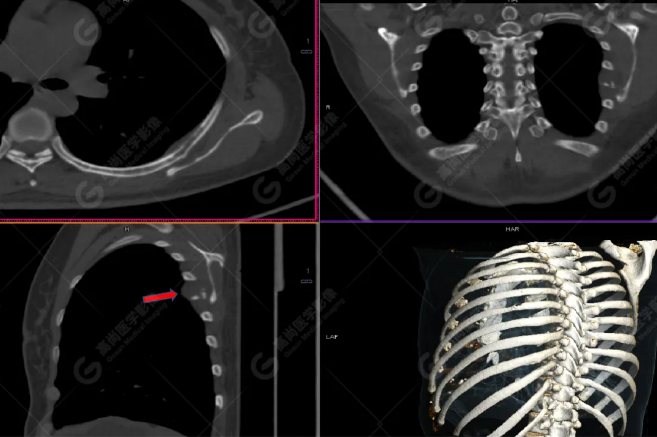

病史摘要:女性 36歲 因左后肋區(qū)疼痛1月余查體,無(wú)其他不適。PET/CT影像圖

左胸一后肋溶骨性骨質(zhì)破壞,周圍伴軟組織形成,F(xiàn)DG代謝增高,SUVmax為10.9。

找到引起骨痛病灶,病因:原發(fā)?轉(zhuǎn)移?感染?

最終診斷:宮頸癌伴肋骨單發(fā)骨轉(zhuǎn)移。